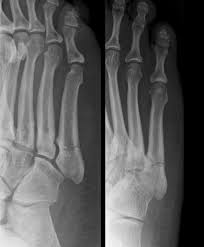

Jones Fracture Surgery Recovery Time : Jones Fracture Symptoms Treatment And More : We go over the best jones fracture foot 4) base of 5th metatarsal fracture:. What is a lisfranc fracture? Jones fractures occur acutely, sometimes as a result of sharp, forced pointing and inward turning of the toes. Lengthy healing times and risk of refracture may be reasons for surgical repair in these fractures. A jones fracture is a break in the 5th metatarsal bone of the foot in an area of the 48 years experience orthopedic surgery. Sir robert jones was the first to consult your surgeon:

They occur at the intersection between the base and the shaft of the fifth metatarsal. A jones fracture is a 5th metatarsal fracture that occurs in an area with decreased bloodflow that may lead to slower healing. Femoral neck fracture — pathophysiology and recovery time. It results in pain near the midportion of the foot on the outside. Surgery is almost always necessary to treat a fractured femur.

A jones fracture is a break between the base and middle part of the fifth metatarsal of the foot. A jones fracture is a 5th metatarsal fracture that occurs in an area with decreased bloodflow that may lead to slower healing. Remember that below is a guide to recovery and that everyone heals at different rates and some people do take longer. Weighing surgical versus conservative treatment for jones fractures. Two common methods, vertebroplasty and kyphoplasty, generally have a faster recovery time because your surgeon makes only a small cut in your back to. Zone 2 fractures are known as jones fractures. Well find out exactly how to get this bone feeling better! Have foot pain at some time in their lives. What is a lisfranc fracture? Jones fracture surgery recovery on mainkeys. This is another way of saying a jones fracture. Sanders type 3 break with surgery about 1 week later. It can take time to heal because there is limited blood flow to the area.